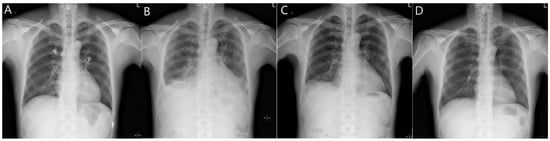

Although we were unable to obtain the gas and dust samples he may have inhaled by measuring the working environment, or determine zinc particles in the lungs (bronchoalveolar lavage fluid or tissue), we diagnosed acute lung injury induced by the inhalation of zinc or zinc oxide fumes based on the obtained findings and the patient’s clinical course. A high-dose steroid therapy (methylprednisolone 31.25 mg/day) was started on day 7 of admission. The patient’s headaches and respiratory symptoms were relieved from the third day after steroid administration (day 10 of admission). He was discharged on day 14 of admission based on the chest X-ray imaging results, and his subjective symptoms remarkably improved as the levels of serum markers decreased. However, pulmonary function testing on the day of discharge revealed a persistent restrictive ventilation defect (FVC, 60%; FEV1, 61%; FEV1/FVC, 80%). During an outpatient visit 7 days after discharge, the patient had normalized serum inflammatory levels and significantly improved pulmonary edema (Figure 2).

Figure 2. Changes in plain chest radiography (PA) with the clinical course. (A) No active disease at the time of admission. (B) Deterioration during hospitalization (6 days after admission); pneumonia or pulmonary edema; bilateral pleural effusion or thickening. (C) Improvement in pulmonary edema 13 days after admission. (D) No active disease at the time of outpatient follow-up (7 days after discharge).